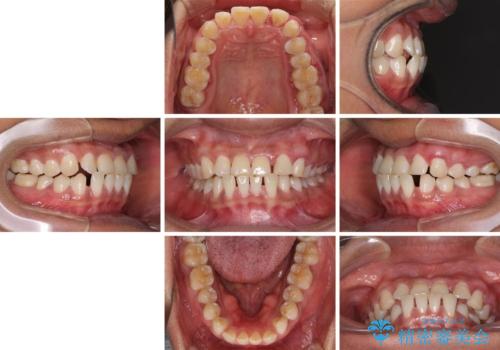

反対咬合の改善 途中で出産をしながらワイヤー矯正

- 前歯の隙間と反対咬合を気にして来院された患者様です。

マウスピース矯正も提案しましたが、しっかりと使用する自信がないとのことで、ワイヤー装置により矯正治療を行うこととしました。